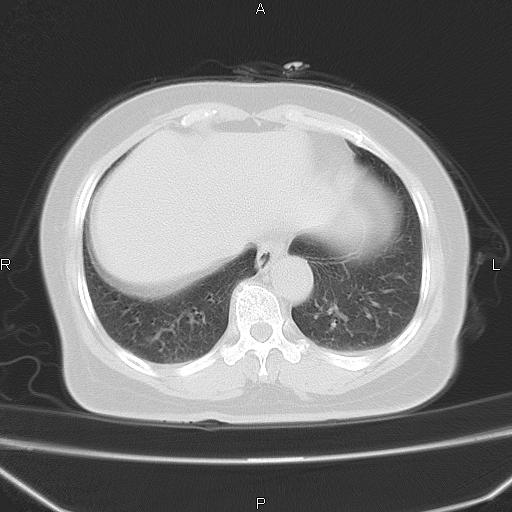

胸腺瘤

女、63Y 双眼睑下垂,早轻晚重。 胸腺瘤???

结果胸腺瘤